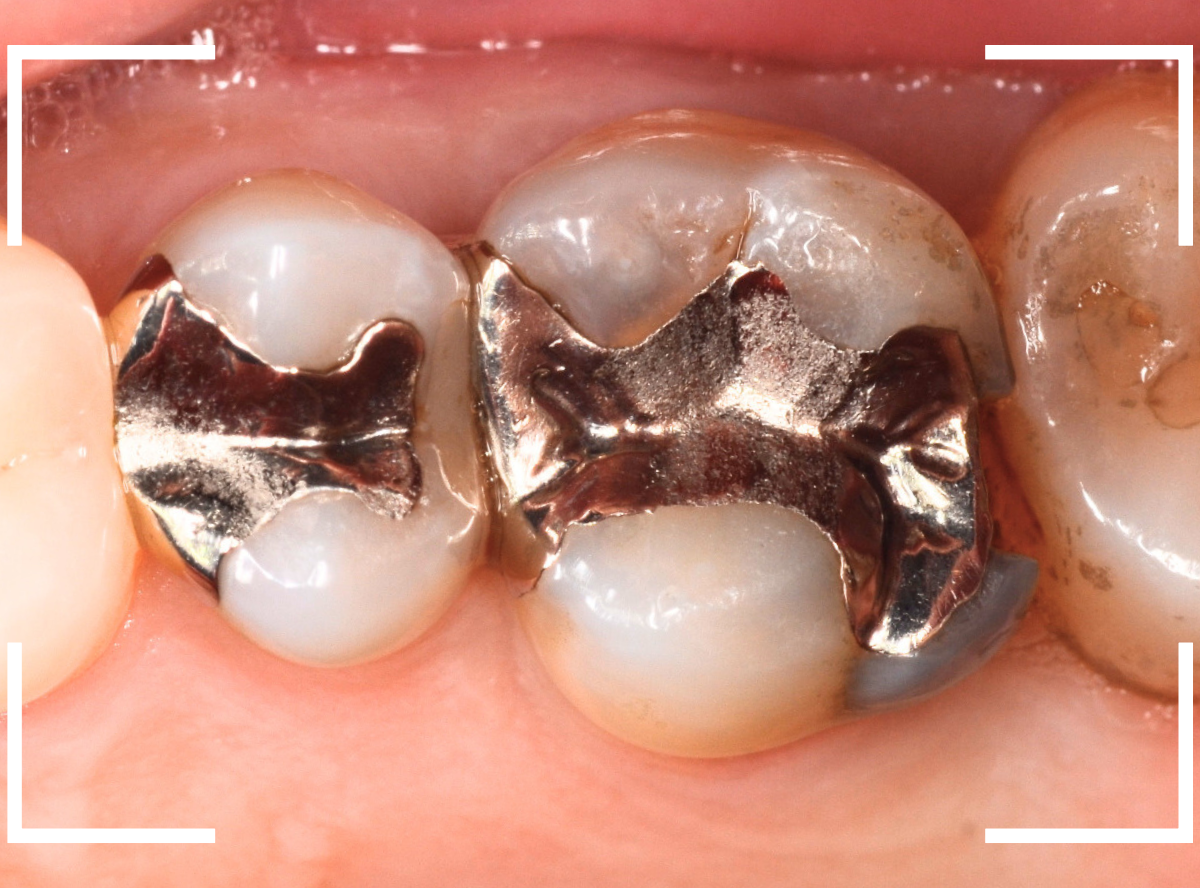

「下の奥歯の銀歯を白くしたい」というご希望の患者さんです。

メタル・インレーとメタル・クラウンが入っていますね。

検査の結果、再製に問題なさそうでしたので、治療を進める事になりました。

まずは、奥のメタル・クラウンを外します。

メタル・コアが入っていますが、こちらも慎重に外して、中を調べていきます。

レントゲン写真では問題なさそうでしたが、メタルコアを除去すると、中は真っ黒でした。

このように、コアの中で虫歯が進行している場合もありますので、さし歯をやり直す際は、出来る限りコアも外して調べるようにしています。

治療前後の写真になります。

やはり、印象が大きく変わりますね。